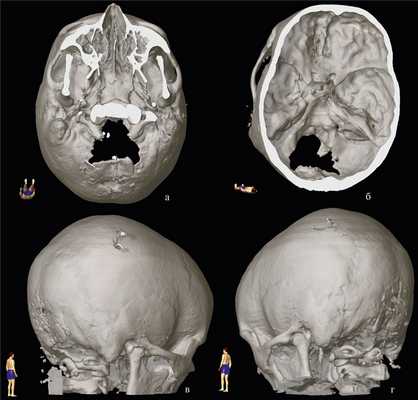

Рис. 3. Данные К.Т. спустя 12 ч после операции; 3-мерная реконструкция. а — вид снизу; б — вид изнутри полости черепа; в — вид сзади и справа; г — вид сзади и слева (костный лоскут выделен пунктиром).

Послеоперационное течение. Течение послеоперационного периода было гладким, осложнений не отмечено. Компьютерная томография спустя 12 ч после операции подтвердила удовлетворительное положение костного лоскута (см. рис. 1, б, в. и рис. 3). Пациентка выписана домой спустя 36 ч после операции и вернулась к занятиям в школе через неделю после нее. При контрольном осмотре спустя 3 мес после операции она отметила полный регресс головной боли, боли в шейно-затылочной области, приступы судорог после операции также не повторялись. МРТ головного мозга через 3 мес после операции (см. рис. 1, г) выявила нормальное положение миндаликов мозжечка, появление просвета большой затылочной цистерны, признаков псевдоменингоцеле не было.